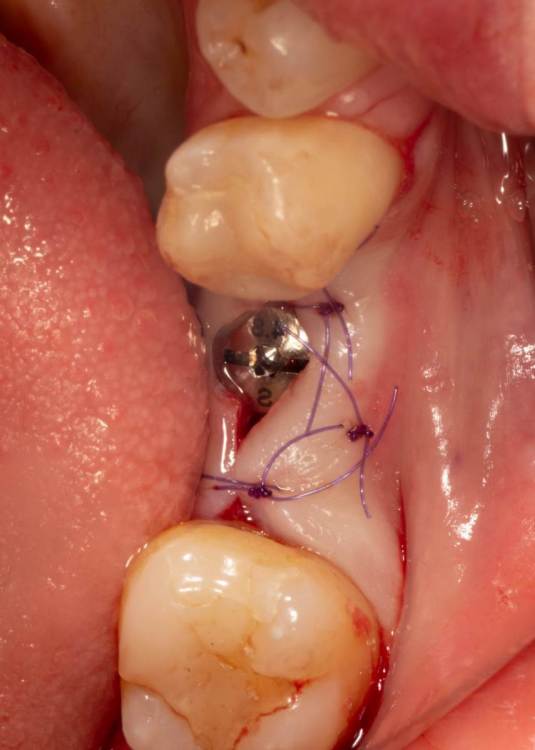

Женька Опубликовано 19 июня, 2023 Поделиться Опубликовано 19 июня, 2023 Здравствуйте, коллеги. Примерно с нового года начал ставить ТЛ имплантаты Дентиум. Что-то под заглушку (не поймал торки, представляете?). Что-то на низких формирвателях. И вот пришла пора протезирования, но отпустить к ортопеду не подготовив десну - не получается. Создал сам себе проблем, сегодня вот исправлял. Получилось неплохо? 3 Ссылка на комментарий

TIGER Опубликовано 20 июня, 2023 Поделиться Опубликовано 20 июня, 2023 Это ж не TL,cубкрестально же.А так я бы длиннее брал ССТ,с захватом соседей Ссылка на комментарий

Женька Опубликовано 20 июня, 2023 Автор Поделиться Опубликовано 20 июня, 2023 @TIGER в смысле это не ТЛ?))) Фото с редукцией не сделал. А то что, шейку погружал - так нужно было. Но это ТЛ. Поверьте) я был на имплантации) Ссылка на комментарий

АнтонТЛТ Опубликовано 20 июня, 2023 Поделиться Опубликовано 20 июня, 2023 Думаю имеется ввиду что имплантат TL установлен по протоколу BL Ссылка на комментарий

Женька Опубликовано 20 июня, 2023 Автор Поделиться Опубликовано 20 июня, 2023 @АнтонТЛТ мы же позиционируем платформу относительно зенита? Есть ли разница тогда, какой имплантат мы выбираем? Вообще весь смысл здесь был заложен в том, что толщина гребня была не очень. Хотелось поставить тонкий имплантат 3.6. Но рисковать тонкой платформой не хотелось, поэтому выбор пал на 4.8 платформу ТЛ и тело имплантата 3.6 1 Ссылка на комментарий

АнтонТЛТ Опубликовано 20 июня, 2023 Поделиться Опубликовано 20 июня, 2023 Конечно относительно зенита, не вдаваясь в подробности, для BL глубже зенита на 3мм, для TL вровень с зенитом. Ссылка на комментарий